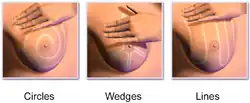

The woman then palpates her breasts with the pads of her fingers to feel for lumps (either superficial or deeper in tissue) or soreness. There are several common patterns, which are designed to ensure complete coverage. The vertical strip pattern involves moving the fingers up and down over the breast. The pie-wedge pattern starts at the nipple and moves outward. The circular pattern involves moving the fingers in concentric circles from the nipple outward. Some guidelines suggest mentally dividing the breast into four quadrants and checking each quadrant separately. The palpation process covers the entire breast, including the "axillary tail" of each breast that extends toward the axilla (armpit). This is usually done once while standing in front of the mirror and again while lying down.